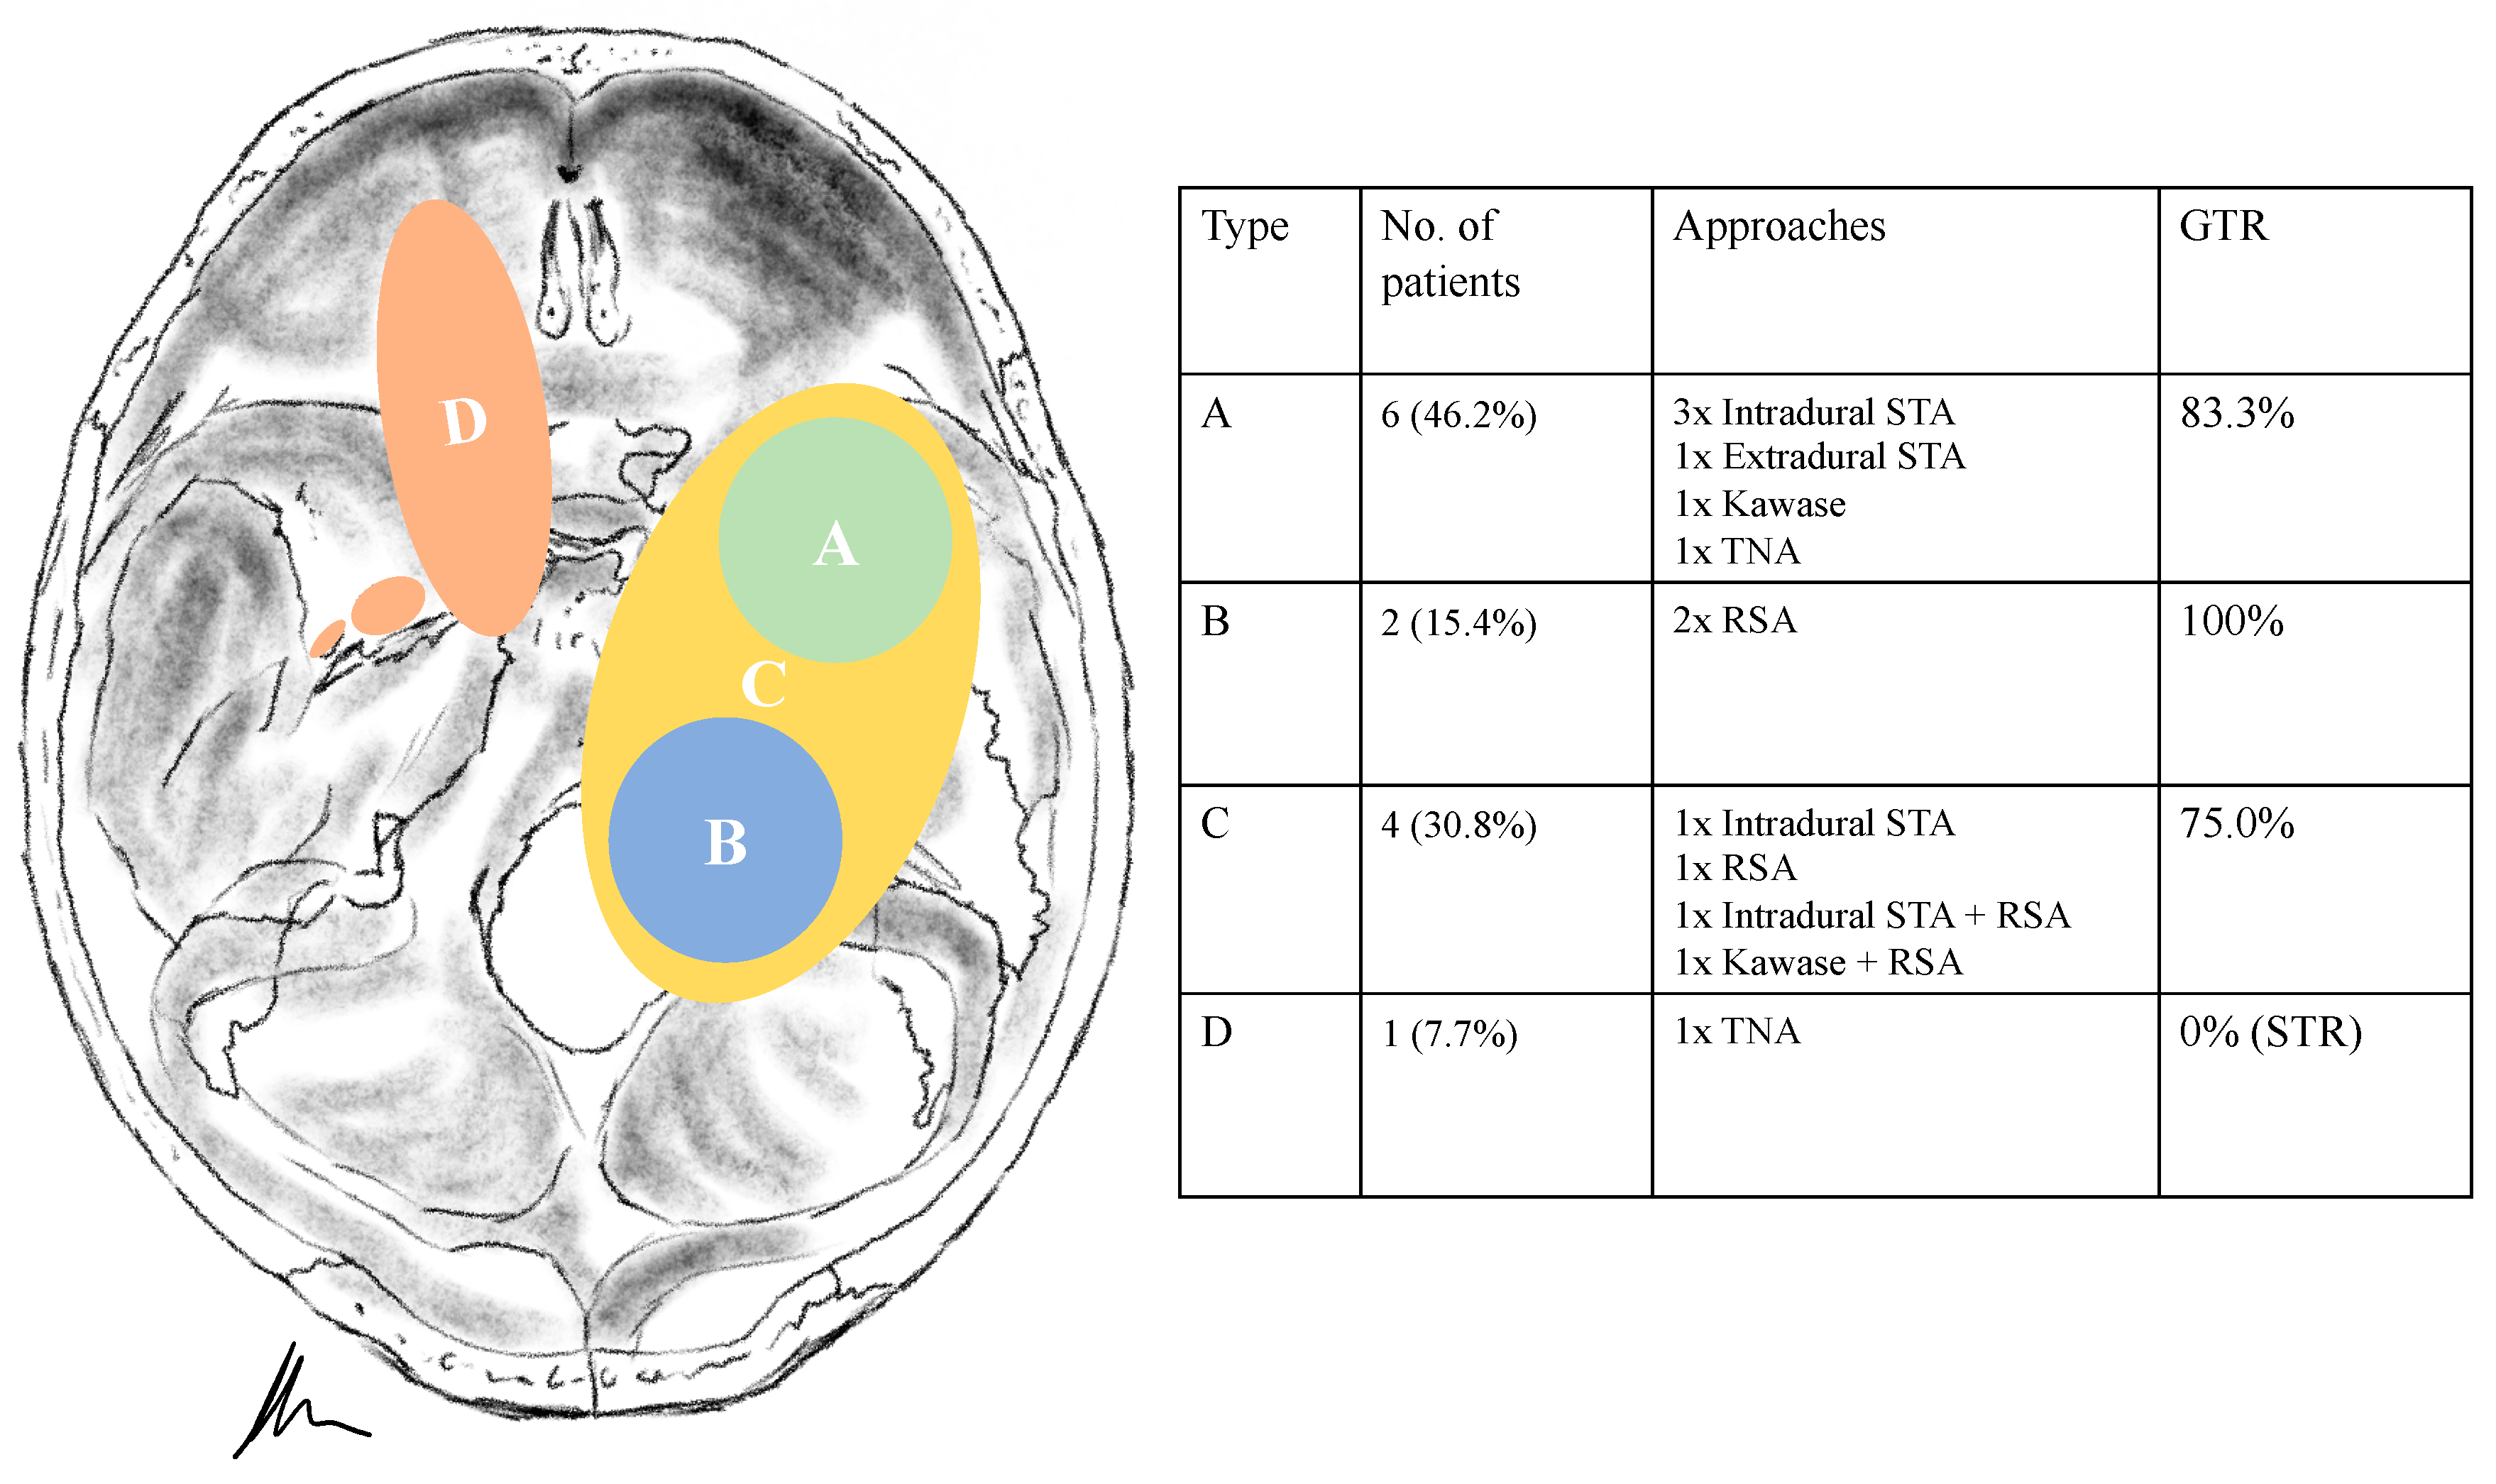

Tumour locations were classified according to Samii’s and Ramina’s classification [5,6]. According to Samii et al. (Table 2), six schwannomas were classified as Type A, two as Type B, four as Type C and one as Type D. In two cases, the tumor was resected in a two-stage technique. The intradural subtemporal approach was performed in five cases, the extradural technique once, the retrosigmoid in five cases, the Kawase and a transnasal approach in two cases, respectively. The two cases with a two-stage approach (one neurofibromatosis type 2 (NF2) patient, Figure 1) were classified as Type E, according to Ramina et al., reflecting the surgical difficulty [6].

Figure 4. A 39-year-old male patient with neurofibromatosis type 2 presented with progressive vertigo, intermittent right facial pain and trigeminal hypesthesia (V1). (A) Preoperative axial and (B) coronal T1-weighted gadolinium-enhanced MRI, showing an impressive space-occupying cystic trigeminal schwannoma, involving the middle (MF) and posterior fossa (PF) through Meckel’s cave (Samii Type C). (C) Postoperative axial and (D) coronal MRI control, indicating complete resection via a two-stage technique; a modified Kawase and a retrosigmoid approach were performed. Postoperatively, no new deficits occurred and the patient recovered from the facial pain.